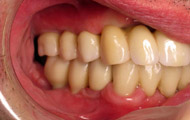

Situation clinique initiale

Situation clinique terminée